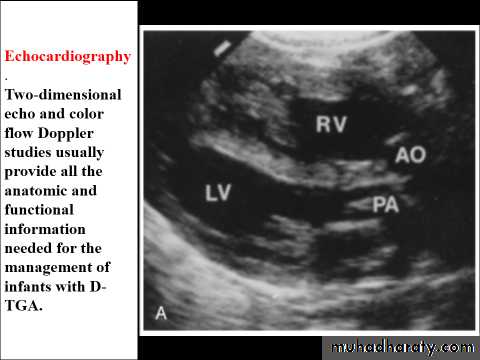

T.G.A represents about 5% of congenital heart defects, and it is the most common cyanotic lesion to present in the Newborn period . T.G.A is ventriculoarterial discordance secondary to abnormalities of septation of the truncus arteriosus, the aorta arises from the right ventricle, anterior and to the right of the pulmonary artery, which arises from the left

ventricle. This transposition results in desaturated blood returning to the right heart and being pumped back out to the body, while well-oxygenated blood returning from the lungs enters the left heart and is pumped back to the lungs. Without mixing of the two circulations, death occurs quickly. Mixing can occur at the atrial (patent foramen ovale/ASD), ventricular (VSD), or great vessel (PDA) level